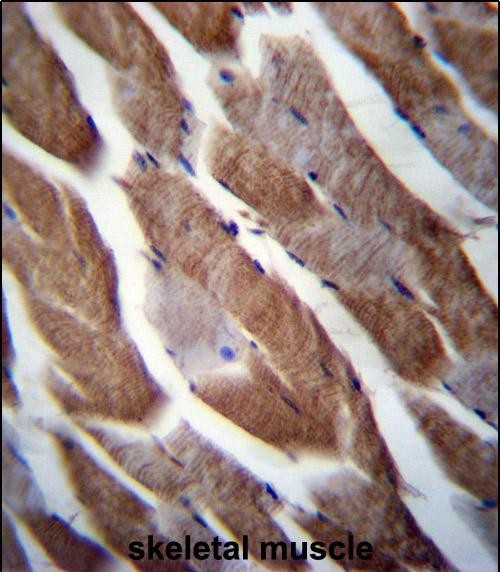

IHC 1/100-1/500 Human,Mouse,Rat

The MATN1 antibody targets matrilin-1. a cartilage-specific extracellular matrix (ECM) protein encoded by the *MATN1* gene. Matrilin-1 is a member of the matrilin family, which plays a structural role in ECM organization and mediates interactions between collagen fibrils and other ECM components, such as cartilage oligomeric matrix protein (COMP). It is predominantly expressed in developing and adult hyaline cartilage, contributing to skeletal development, chondrocyte differentiation, and tissue resilience. MATN1 antibodies are widely used in research to study cartilage biology, skeletal disorders (e.g., osteoarthritis, chondrodysplasias), and ECM remodeling processes. These antibodies enable the detection of matrilin-1 localization, expression levels, and post-translational modifications via techniques like immunohistochemistry, Western blotting, or immunofluorescence. Studies using MATN1 antibodies have revealed its reduced expression in degenerative cartilage diseases, suggesting its role as a biomarker or therapeutic target. Additionally, they aid in investigating genetic mutations linked to skeletal malformations. Commercial MATN1 antibodies are typically validated for specificity in human, mouse, or rat tissues, supporting both basic and translational research in orthopedics, developmental biology, and connective tissue pathologies.